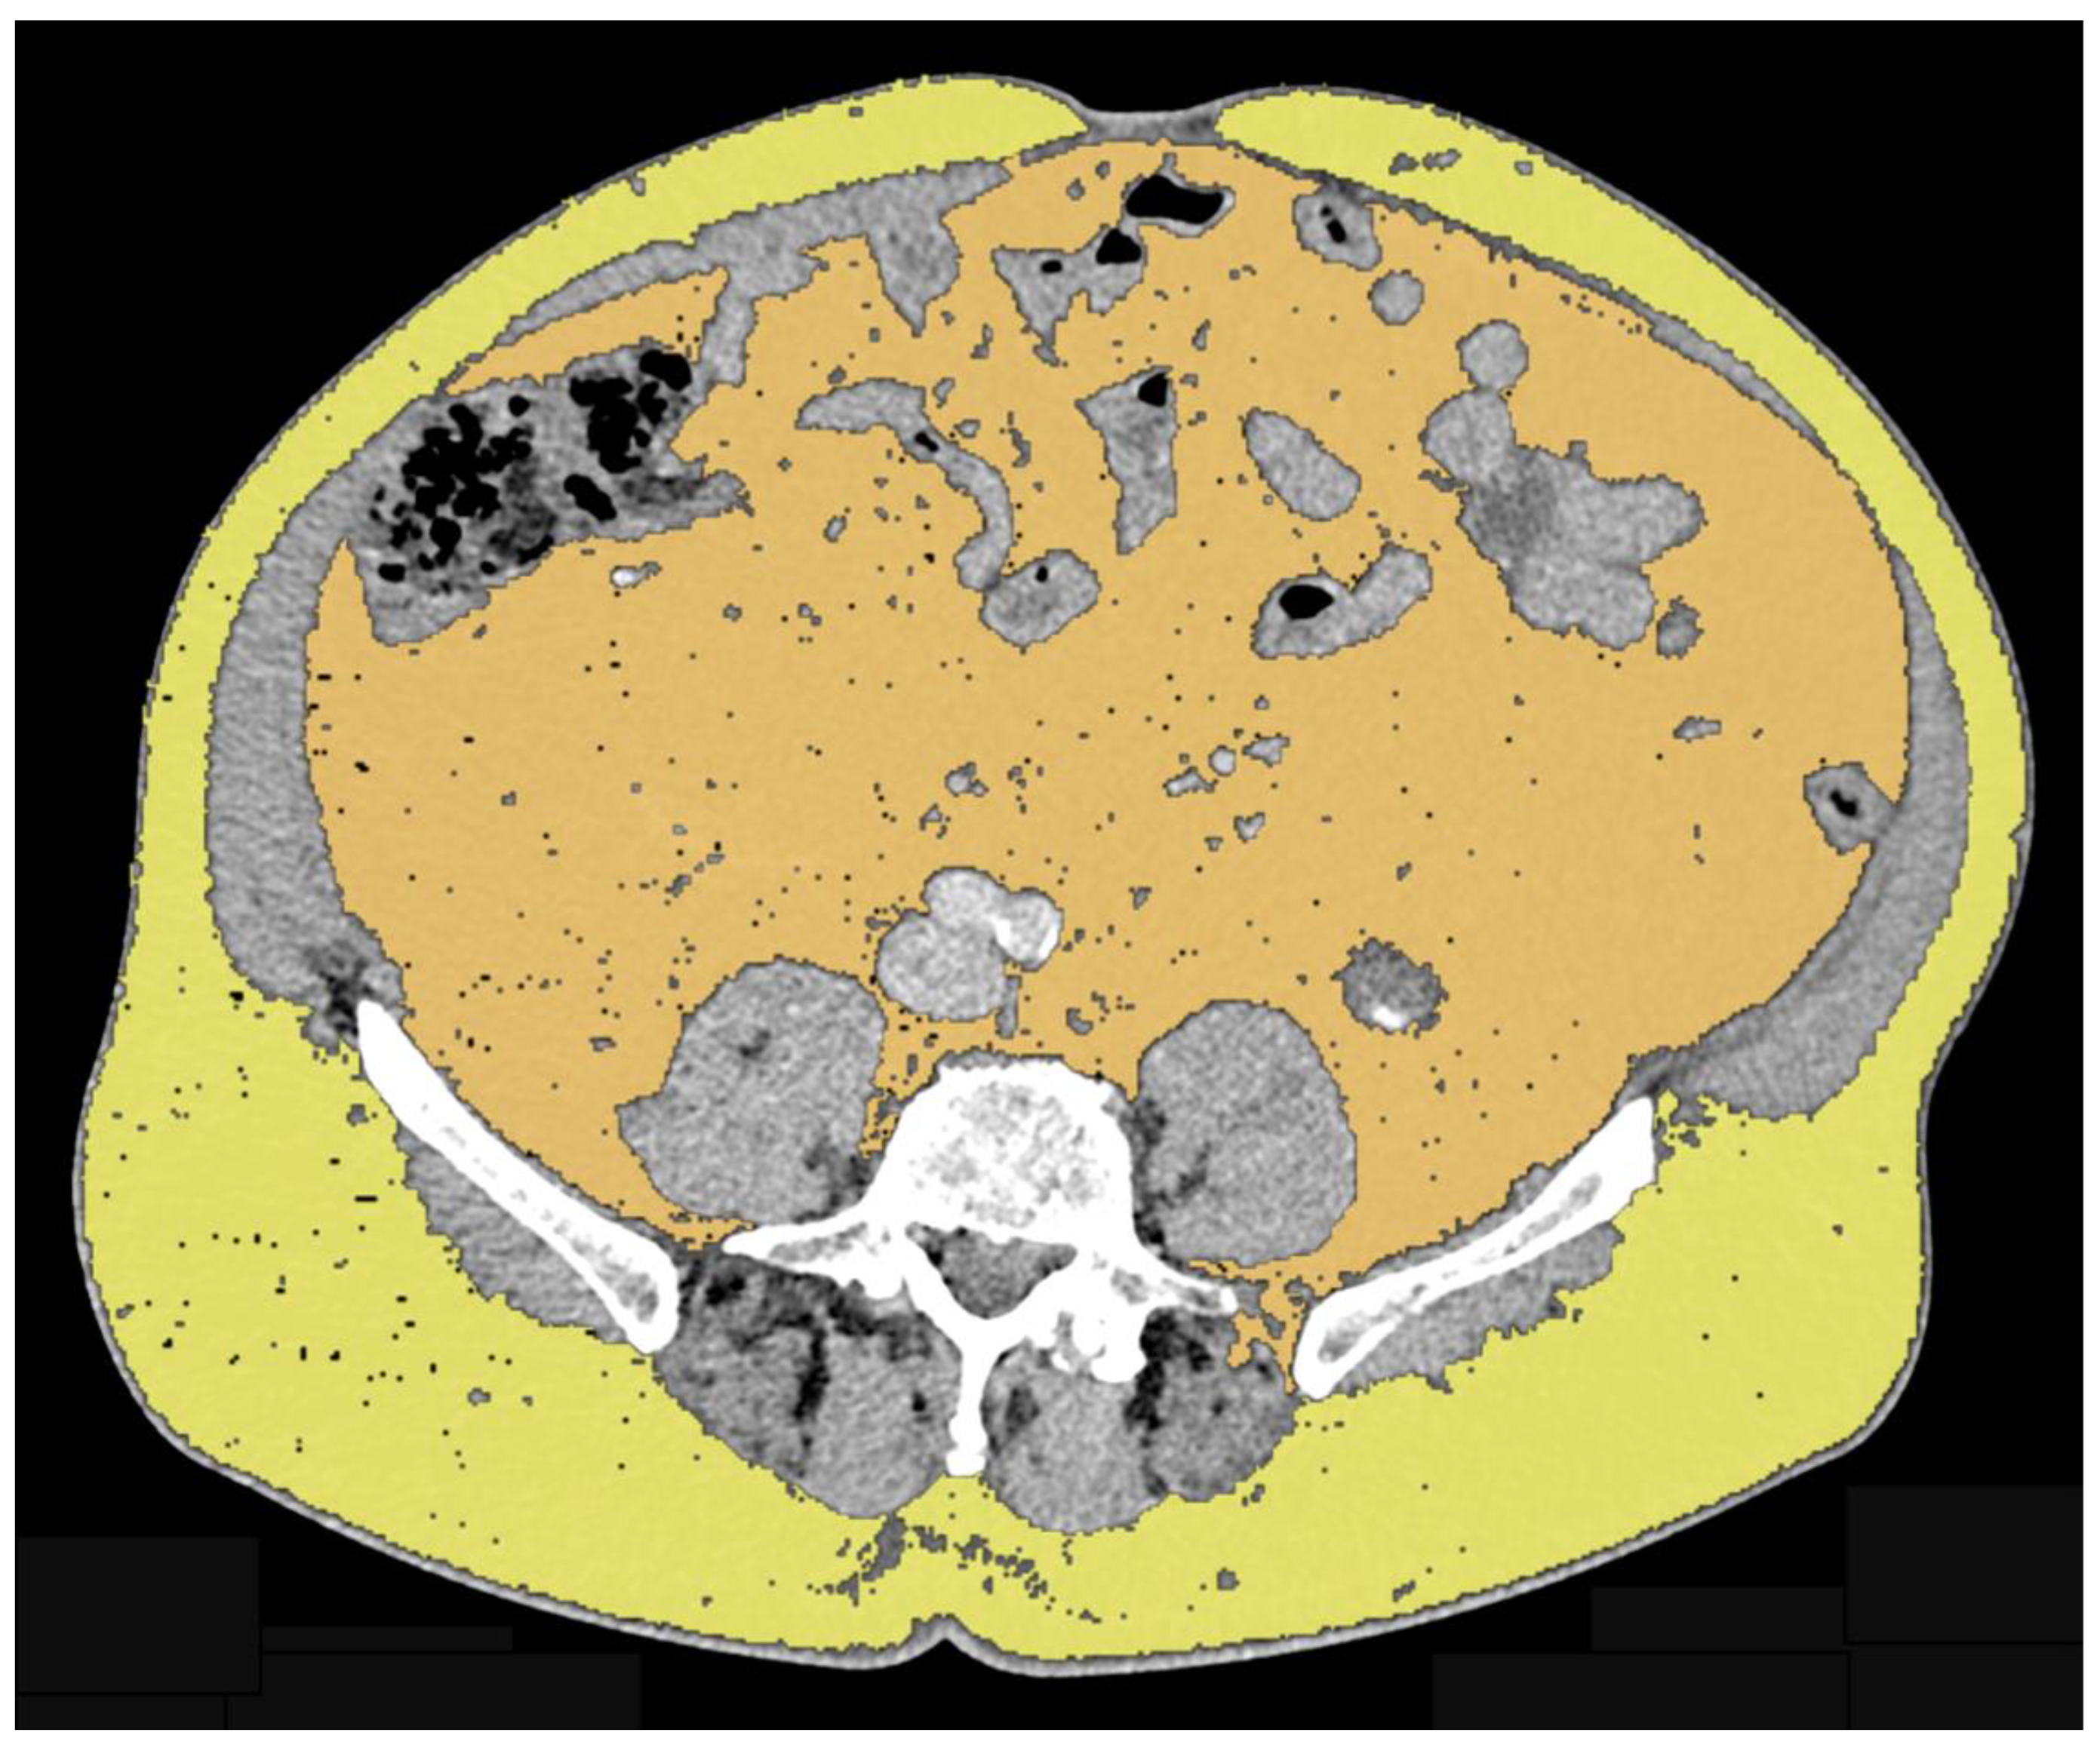

Androgens play an active role in body composition in men. Indeed, a positive correlation has been found between serum testosterone concentrations and lean mass together with a negative correlation with fat mass [1]. Testosterone replacement therapy determines an increase in lean body mass and a decrease in fat mass in hypogonadal men [2,3]. Surgical androgen deprivation or medical castration were the basis for treatment of advanced prostate cancer [4]. The new cytotoxic and androgen receptor-targeted therapies have demonstrated a survival benefit in association with androgen deprivation [5]. Considering that androgens are important for the homeostasis of different organ systems, their use is related to a number of harmful effects [6]. One of the side effects of androgen deprivation therapy (ADT), even for short term treatment, is an increase of fat mass [7,8]. The absence of androgen-related hormones changes the lipid composition of tissues and decreased insulin sensitivity, resulting in the promotion of an obese-like phenotype [9,10]. A body mass index (BMI) greater than 30 kg/m2 defines obesity, but it does not provide information on body composition such as the quantity of the different adipose tissue compartments [11,12]. Fat compartments can be distinguished by computed tomography (CT) and magnetic resonance imaging (MRI), non-invasive imaging techniques for qualitative and quantitative analysis of tissues (Figure 1 and Figure 2) [13,14,15,16,17].

Figure 1.

Axial CT image of a male subject showing VAT segmented in orange and SAT segmented in yellow.